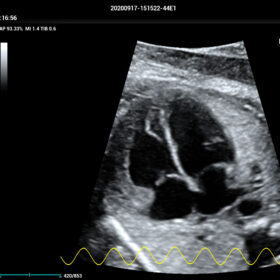

Cardiovascular Solution

- Auto EF– Automatic measurement of ejection fraction by diastole/systole frames

- TTQA-Myocardial sychronization evaluation with quantitive analysis

- RIMT-RF data based real-time IMT measurement